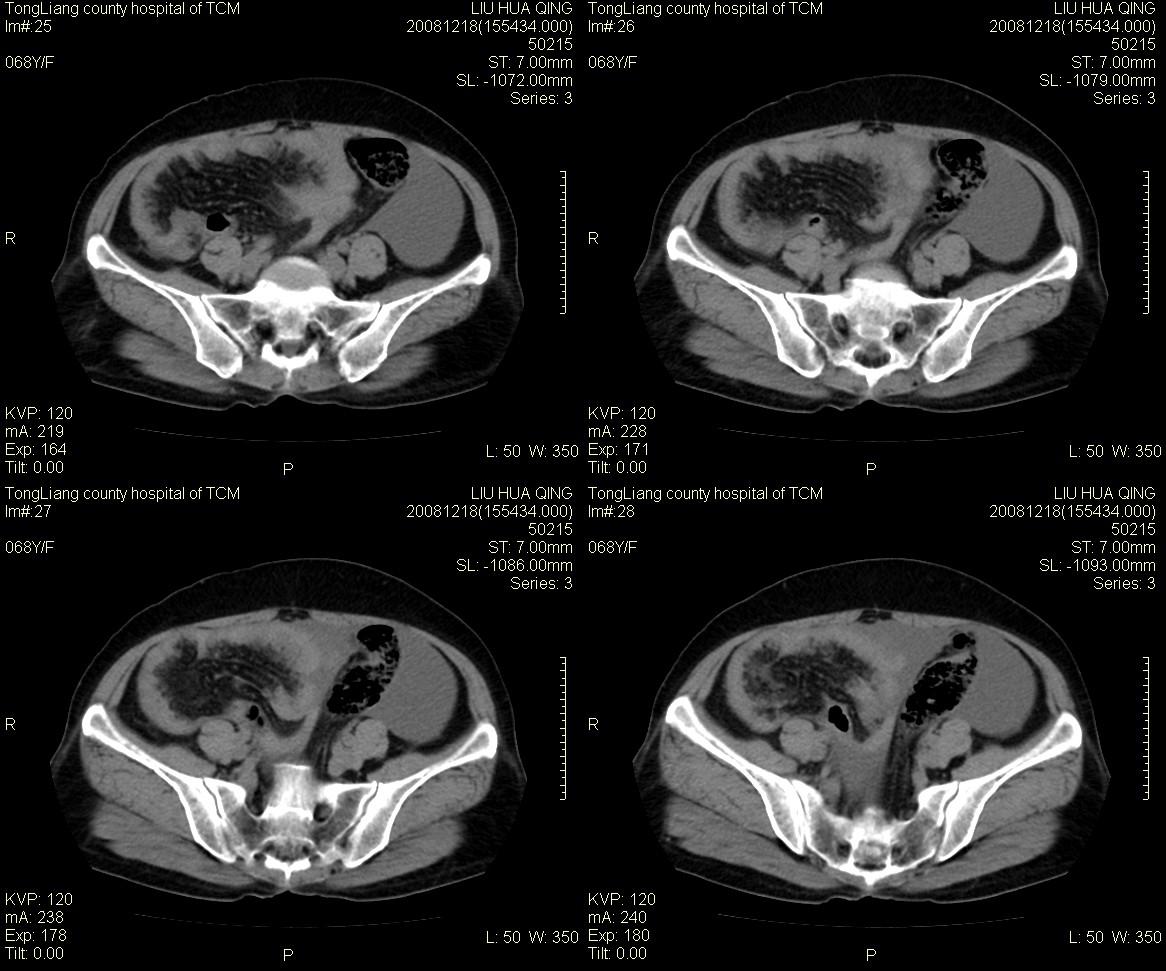

女,68y,下腹疼3月,一月半前院外ct示上腹未见异常。近1月来,症状加重。4天前入院,b超示胸腹水。今日呕吐频繁。  生化检查:  结核抗体阴性,血沉18mm/h, 癌胚抗原阴性,胸水细胞学检查见多数淋巴细胞。 白细胞总数5.4x10^12/l,血红蛋白104g/l.

患者右中腹部肠管聚集,内密度不均,可见片絮状及结节样增密影,小肠壁增厚,与之相邻处有软组织影。

腹腔积液可以肯定,原因?右侧下腹肠壁增厚,周围脂肪密度增高,粘连坏死?---梗阻坏死(不像)还是血栓坏死,占位?期待结果。

1)右侧腹腔前部见类似“网膜饼”样改变,考虑网膜转移瘤。2)腹水。

腹膜污染[大网膜增厚可见污垢征及小班结与饼片影,肠系膜增厚],大量腹水。考虑癌性腹膜炎,建议查腹水。结核待排.注意上腹部及胃肠道检查